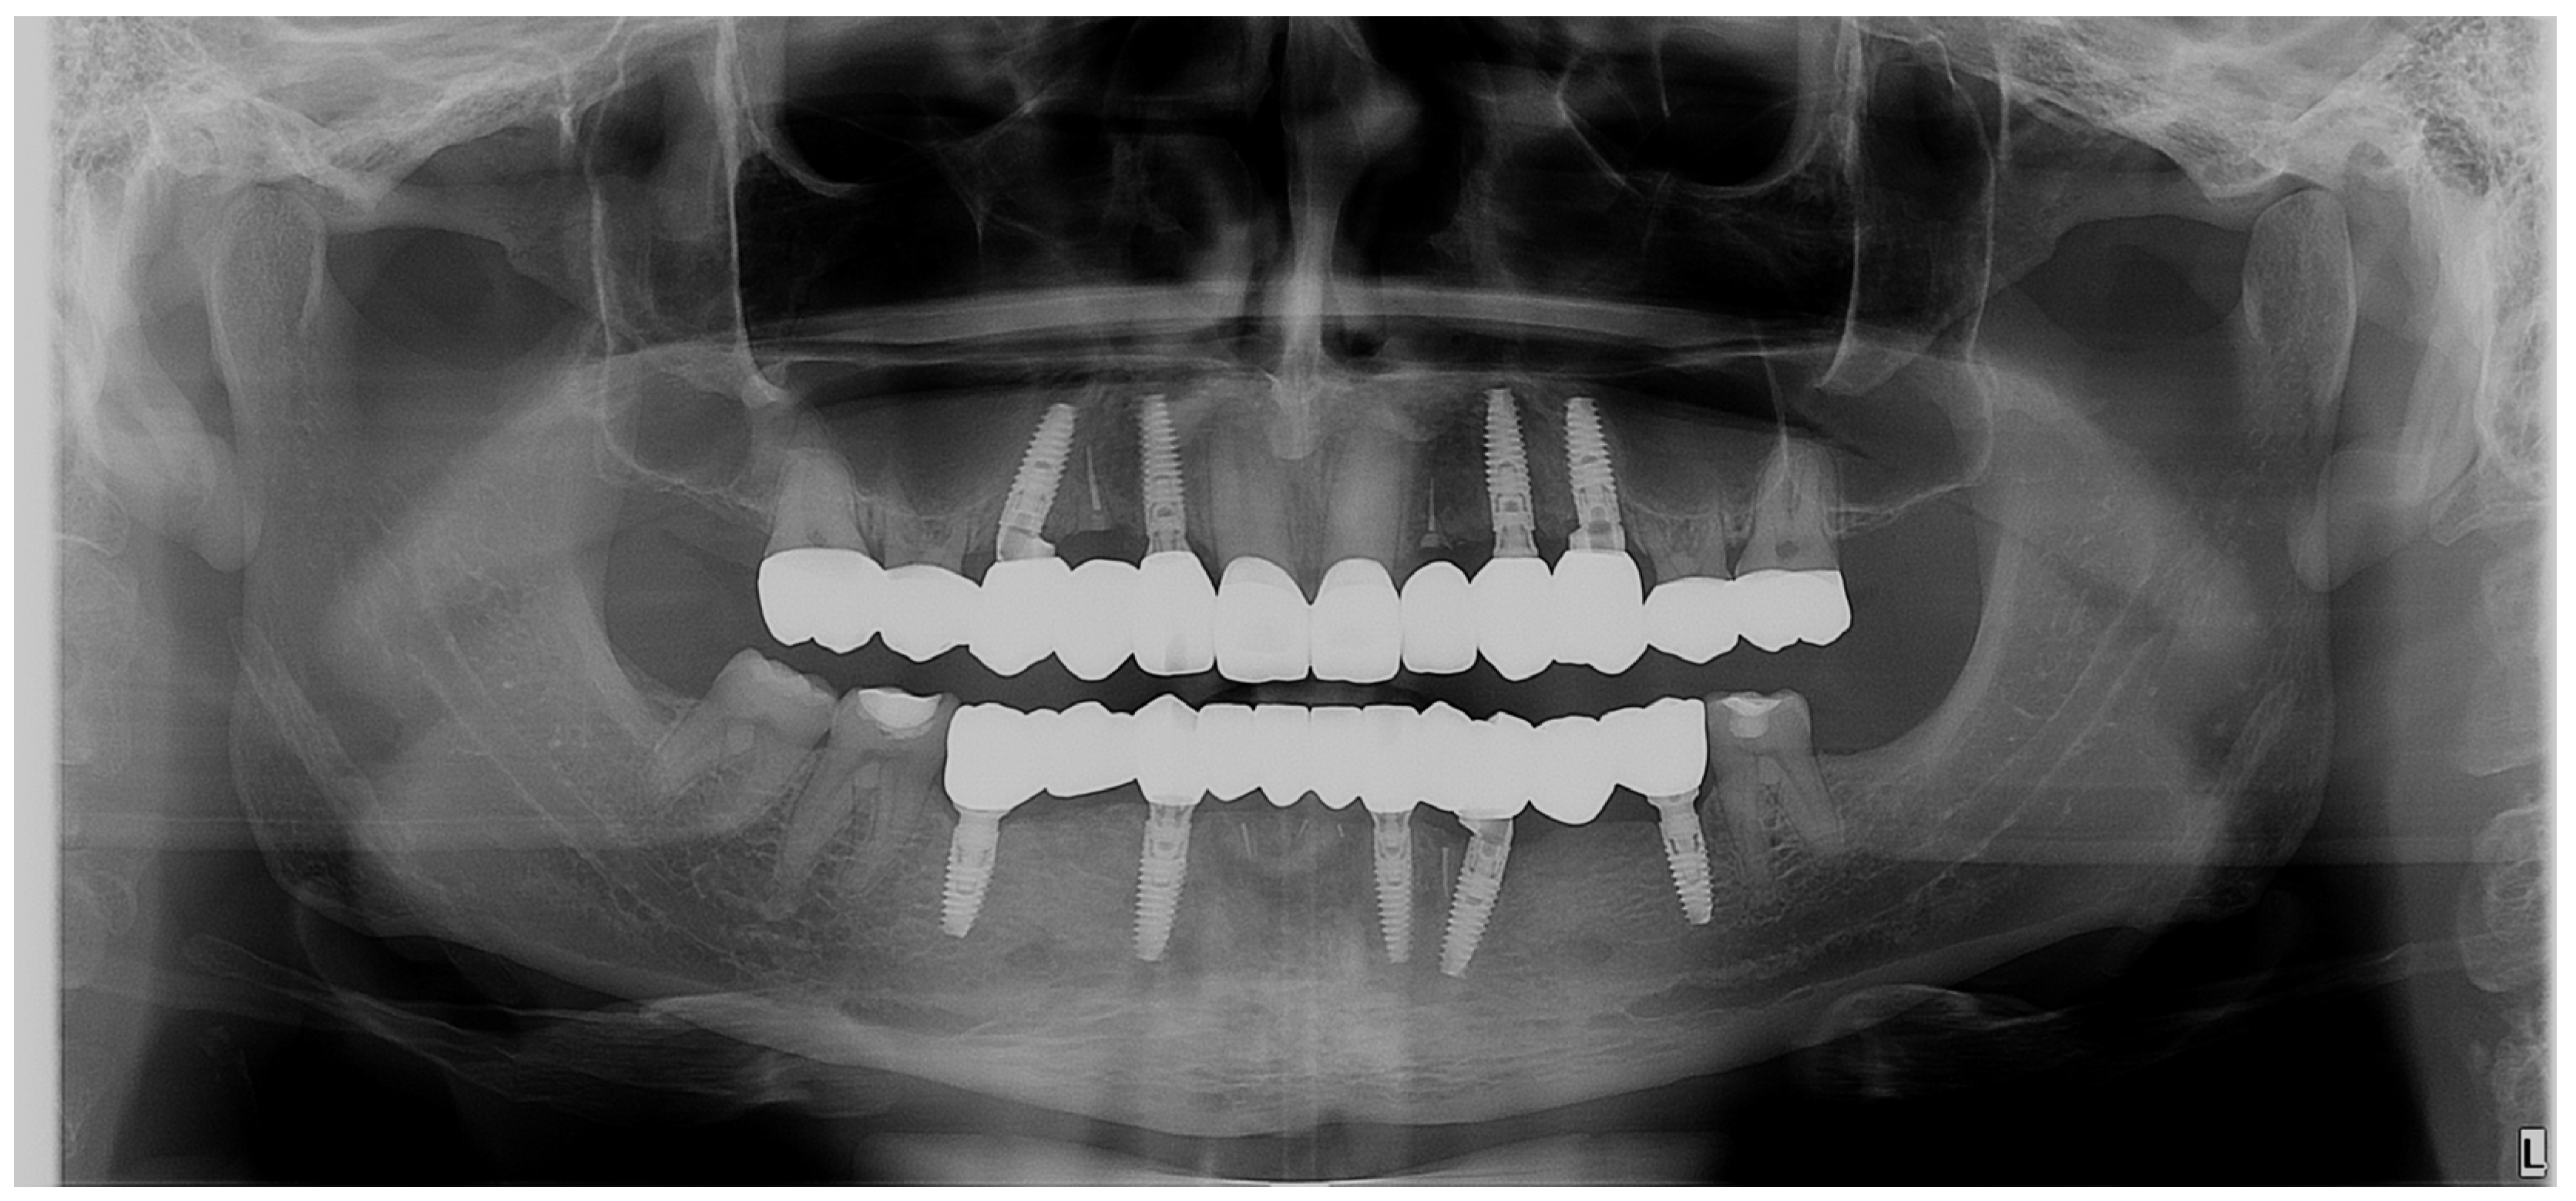

The radiological evaluation (Figure 21) of the final restorations showed good osseointegration of the implants with optimal bony peaks. Also, the submerged roots can be observed for the PET used to maintain the tissues in place.

Figure 21.

Control OPG: the final situation after the implant–prosthetic treatment.